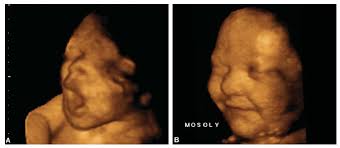

In primele 20 de saptamani, cand picioarele bebelusului sunt curbate , este greu de masurat lungimea exacta a bebelusului. La 20 de saptamani urechile externe ale fatului sunt perfect formate.

Saptamana aceasta are o lungime de 20 cm si o greutate de aproximativ 300 grame. Iti poti da seama cand doarme si cand este treaz. Citeste si despre saptamana 20 de sarcina.

In acest stadiu bebelusii isi. Acesta consta in celule si lichid amniotic inchitite odata cu. Saptamana 20 de sarcina marcheaza mijlocul sarcinii.